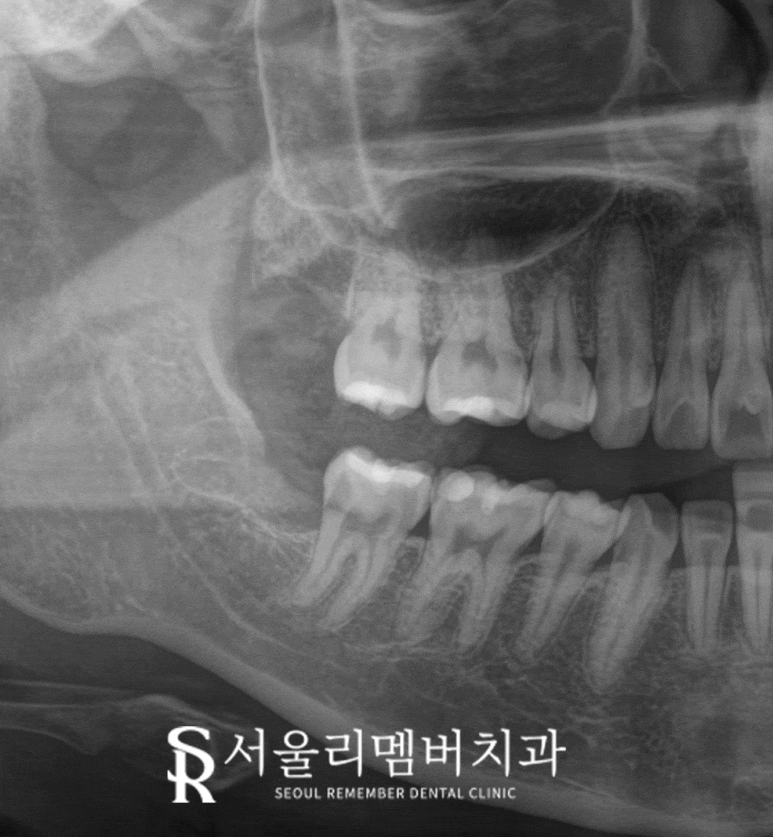

오늘 서울대입구역 치과 에서

보여드리는 케이스는

오른쪽 위아래 사랑니가 모두 존재하는데

하악 제3대구치는 앞으로 기울어져

저작기능을 수행할 수 없으며

되려 그 틈으로 음식물이 끼게 만들고 있습니다.

이 케이스는

하치조 신경과의 거리도 넉넉하고

상악의 경우 수직으로 잘 자라있어

둘 다 당일에 바로 뽑아드렸으며

출혈도 크지 않아

suture 즉, 꿰매지 않고

바로 마무리할 수 있었네요.